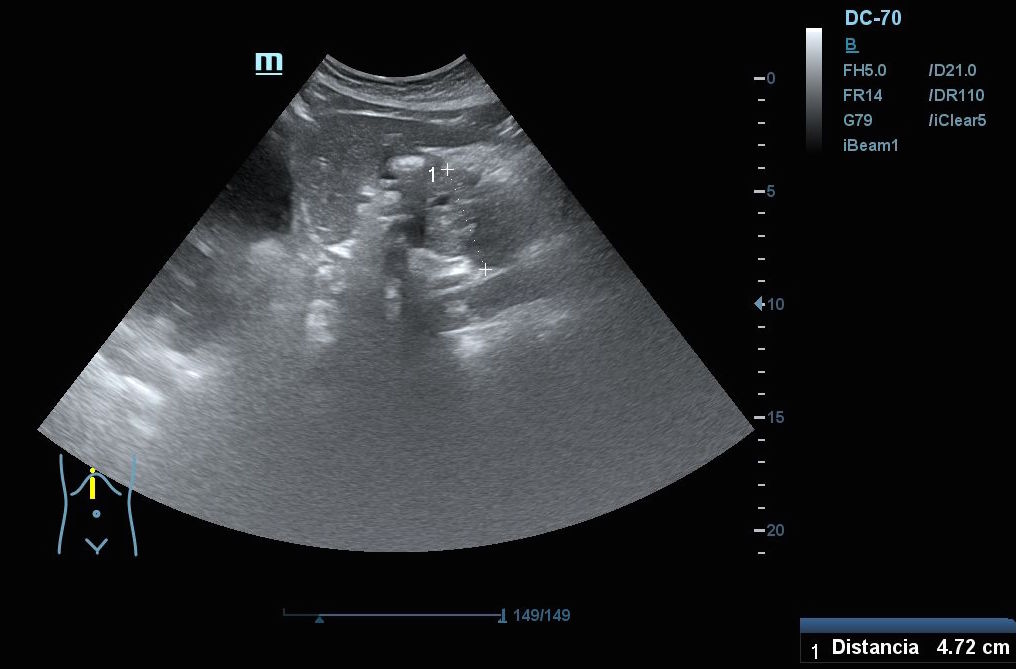

Hallazgos ecográficos: En el epigastrio se observa una imagen anecoica tubular, sin captación en Doppler, con un diámetro mayor a 2 cm, que sugiere una dilatación del colédoco (imagen 1). La vesícula biliar se encuentra completamente distendida y hepatizada, con una imagen en «doble cañón de escopeta» sugestiva de colestasis (imagen 2). En los cortes longitudinales se identifica una masa anterior a la aorta en el corte paramedial izquierdo, aparentemente localizada en el cuerpo del páncreas (imagen 3). En los cortes transversales se observa una masa que afecta tanto al cuerpo como a la cabeza del páncreas (imagen 4).